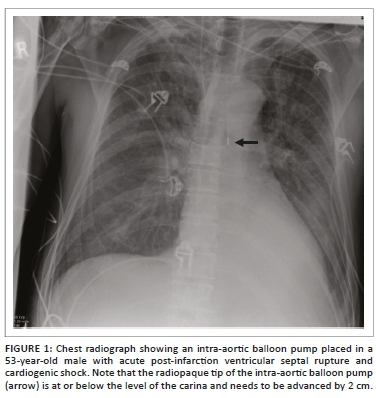

An intra-aortic balloon pump (IABP) is a polyethylene balloon that spans the entire length of the thoracic aorta, placed percutaneously via femoral artery access. The IABP comes in different lengths with IABP selection determined based on the patient's height. The IABP inflates during diastole leading to an increase in blood flow to the coronary arteries, great vessels and renal arteries. Immediately prior to systole, it deflates producing a vacuum effect leading to forward blood flow to the aorta and its branches. Although the IABP is predominately radiolucent on a CXR, it has radiopaque tips proximally and distally. On the CXR, the cephalad radiopaque tip should be 2 cm above the carina (Figure 1). An alternate landmark would be the aorto-pulmonary window. Placing the IABP too caudally may occlude the celiac, superior mesenteric or renal arteries, while placing it too high may occlude the brachiocephalic, subclavian or carotid arteries. Complications that can occur with IABP include vascular (e.g. limb ischaemia, renal insufficiency, mesenteric ischaemia and aortic dissection) and non-vascular (e.g. catheter-related [perforation, tear and incorrect positioning] infection and neurological sequelae).3,4,5